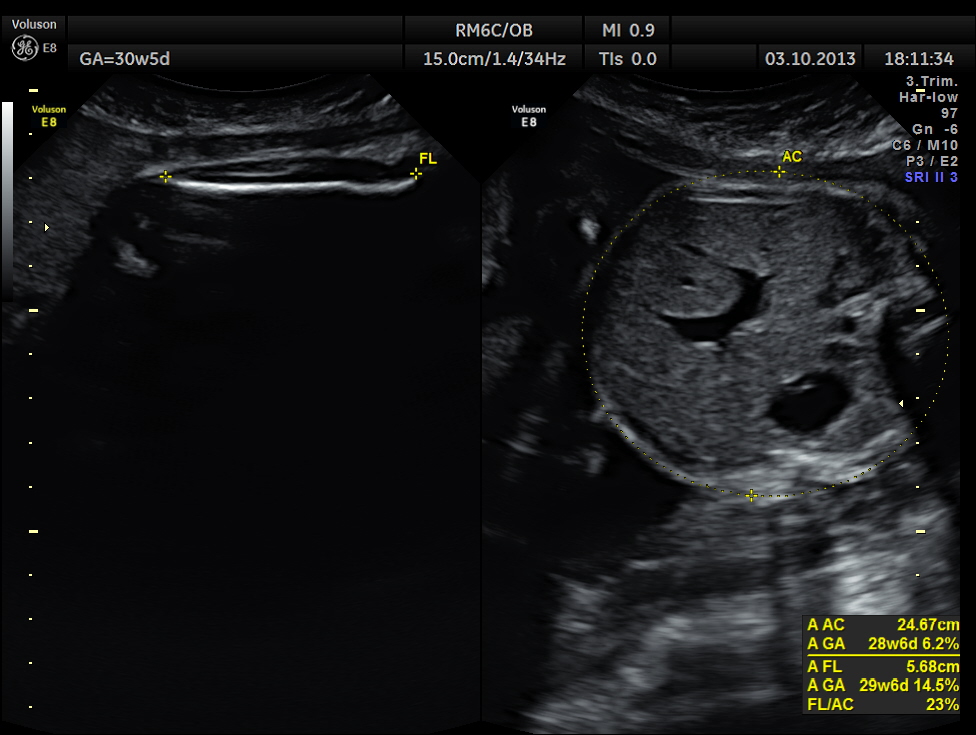

BPD AND HC < 2.3 % TILE suggestive of microcephaly. AC 6.2 % TILE suggestive of growth restriction.

The cerebellum shows 32.1 % tile growth.